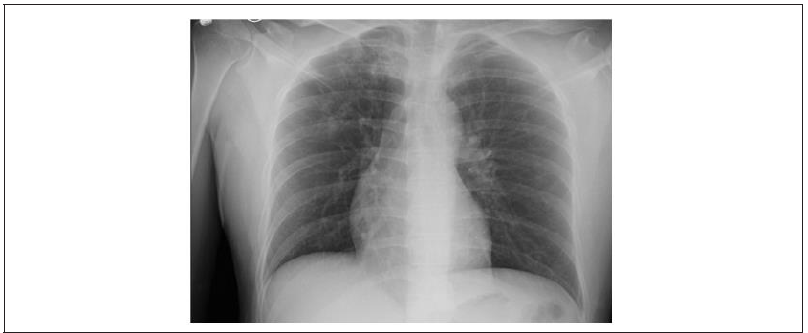

On Imaging CXR (Figure 1) showed a patchy opacity of the right apical lung which warranted further examination with a CT. CT (Figure 2) further highlighted the opacity and showed apical reticulonodular consolidations concerning for mycobacterium species. Patient was scheduled to undergo a bronchoscopy with BAL for sputum cultures and for visualization of any endobronchial lesions.

Figure 1: CXR 1/24/20 1. Patchy opacities of the right apical lung which, when correlated with CT of the chest from the same day, may represent an infectious process including mycobacterium avium or tuberculosis. Correlate clinically.